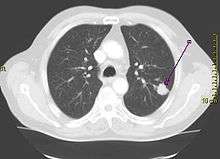

| A chest X-ray showing a tumor in the lung (marked by arrow) | |

Performing a chest radiograph is one of the first investigative steps if a person reports symptoms that may suggest lung cancer. This may reveal an obvious mass, widening of the mediastinum (suggestive of spread to lymph nodes there), atelectasis (collapse), consolidation (pneumonia) or pleural effusion.[1] CT imaging is typically used to provide more information about the type and extent of disease. Bronchoscopy or CT-guided biopsy is often used to sample the tumor for histopathology.[13]

Lung cancer often appears as a solitary pulmonary nodule on a chest radiograph. However, the differential diagnosis is wide. Many other diseases can also give this appearance, including metastatic cancer, hamartomas, and infectious granulomas such as tuberculosis, histoplasmosis and coccidioidomycosis.[61] Lung cancer can also be an incidental finding, as a solitary pulmonary nodule on a chest radiograph or CT scan done for an unrelated reason.[62] The definitive diagnosis of lung cancer is based on histological examination of the suspicious tissue[6] in the context of the clinical and radiological features.[12]